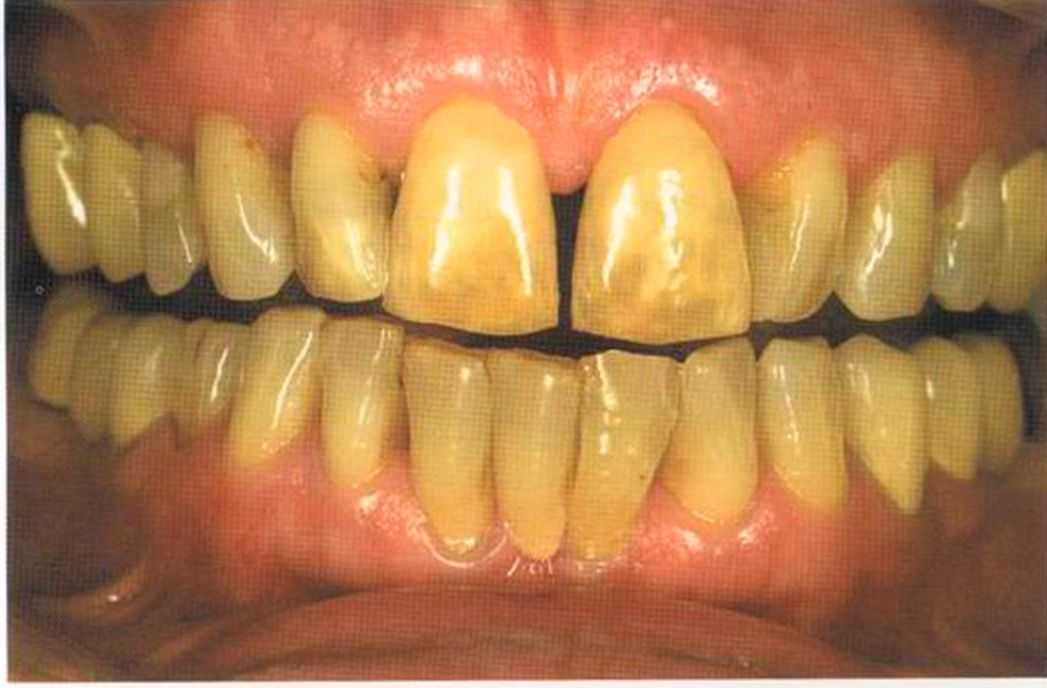

Только что зацементированные коронки. До сих пор сохранилось воспаление десневого сосочка. Уже через несколько дней он будет здоровым, бледно-розового цвета.

Первое лечение проходию много лет назад у другого доктора. Со временем ос те пи / ка уху дин ьась, особенно в пришеечной области. Этот пациент хотел новые коронки в области 12 и 22, по сомневсься, нас кол ько хорошо они будут выглядеть.

Результат с использованием In-Ceram развеял все сомнения, и решение об изготовлении коронки на другой боковой резец не заставило себя долго ждать.